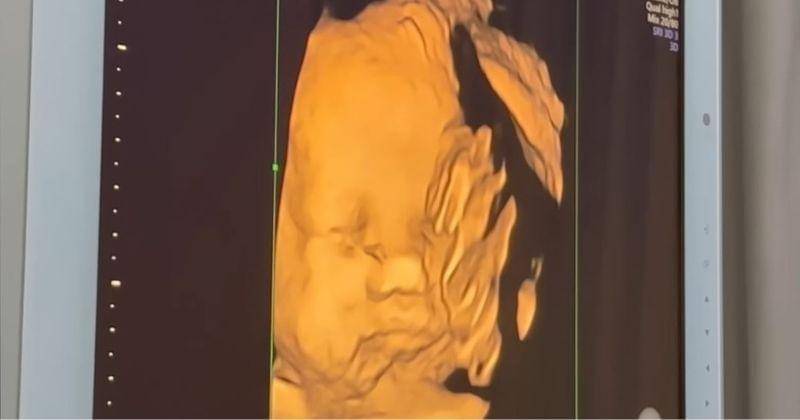

4. Ini dia potret gemas anak kedua Felicya Angelista dan Caesar Hito

Dalam vlog yang diunggah di kanal YouTube-nya ini, Felicya juga sempat melakukan USG untuk melihat wajah anak keduanya. Dokter memeriksa kandungan Felicya dengan USG 3D sehingga wajah sang bayi sempat terlihat cukup jelas.

Felicya dan Hito pun sangat bersyukur saat mengetahui bahwa buah hati yang dikandungnya dalam keadaan sehat dan normal. Keduanya juga sangat bahagia ketika melihat wajah sang bayi di layar monitor USG.

Wah, kira-kira putri kedua Felicya dan Hito ini lebih mirip siapa nih, Ma?